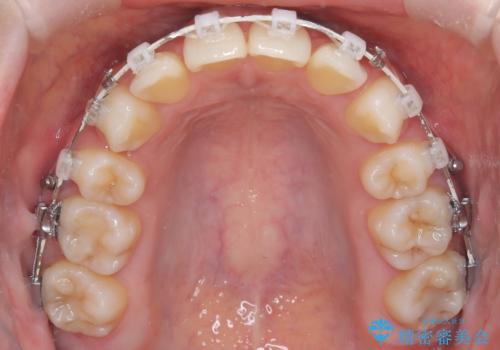

上下4本の抜歯と審美ワイヤー矯正で整った歯並びへ

- 患者様は、歯並びの乱れを整えたいとのことで来院されました。診察の結果、歯列のスペース不足が原因で前歯のガタつきが目立ち、噛み合わせにも影響が出ている状態でした。歯を正しく並べるためにはスペースの確保が必要と判断し、上下の小臼歯4本を抜歯して、審美ワイヤー矯正(白いワイヤーと透明ブラケット)で治療を行う計画を立てました。

まず、抜歯によって歯を動かすためのスペースを確保。その後、審美ワイヤー矯正を用いて、前歯のガタつきを整えながら、噛み合わせの調整も行いました。審美装置を使用することで、矯正中も目立ちにくく、自然な仕上がりを目指して治療を進めました。治療の結果、歯並びがきれいに整い、口元のバランスも改善しました。患者様からは「歯並びがきれいになり、自信を持って笑えるようになった」と喜びの声をいただきました。